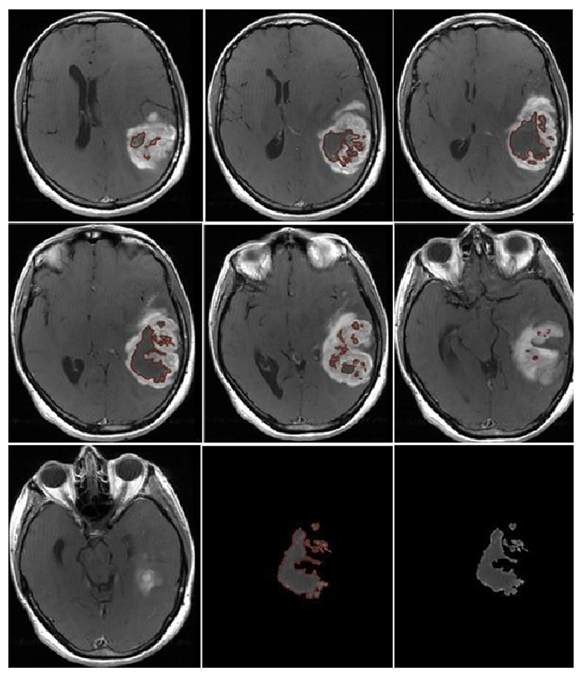

- Morphological appearance: We divided GB lesions into three categories based on the enhancing wall thickness: thin, <3 mm; thin-nodular, when the enhancing wall showed focal thickenings > 3 mm; and nodular, when solid appearance was predominant and intratumoral necrosis was absent or <1.5 cm3. A total of 11 (13%) masses showed a thin pattern, 51 (58%) showed a thin-nodular pattern, and 25 (29%) showed a nodular pattern.

- Multifocal disease: Multifocal disease was found in 20 (23.3%) patients (Table 1).